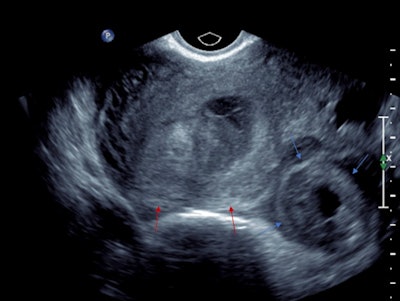

Left adnexal heterogeneous mass with an echogenic tubal ring sign (blue arrows) adjacent to the left ovary (red arrows).

Pelvic free fluid with low-level internal echoes consistent with hemoperitoneum.The patient was given a preliminary diagnosis of a hemorrhagic corpus luteal cyst. Heterotopic pregnancy was initially considered but thought less likely. The treating team opted for conservative management with a view to perform short-term follow-up ultrasound. Follow-up imaging two days later demonstrated a persistent left adnexal mass with interval increase in hemoperitoneum volume. The mass was seen to move separately to the left ovary on transvaginal/abdominal palpation maneuvers.